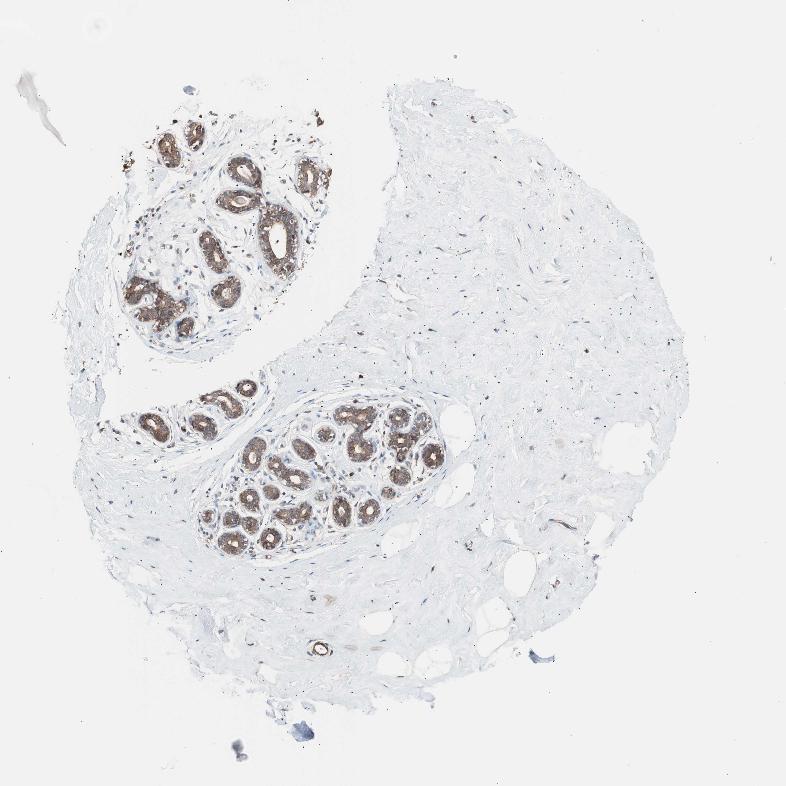

BREAST - Antibody stainingi

Antibody staining in the annotated cell types in the current human tissue is reported as not detected, low, medium, or high, based on conventional immunohistochemistry profiling in selected tissues. This score is based on the combination of the staining intensity and fraction of stained cells.

Each image is clickable and will lead to virtual microscopy that enables deeper exploration of all samples and also displays staining intensity scores, fraction scores and subcellular localization as well as patient and tissue information for each sample.

Antibody HPA006543

Adipocytes Low

Glandular cells High

Myoepithelial cells Medium